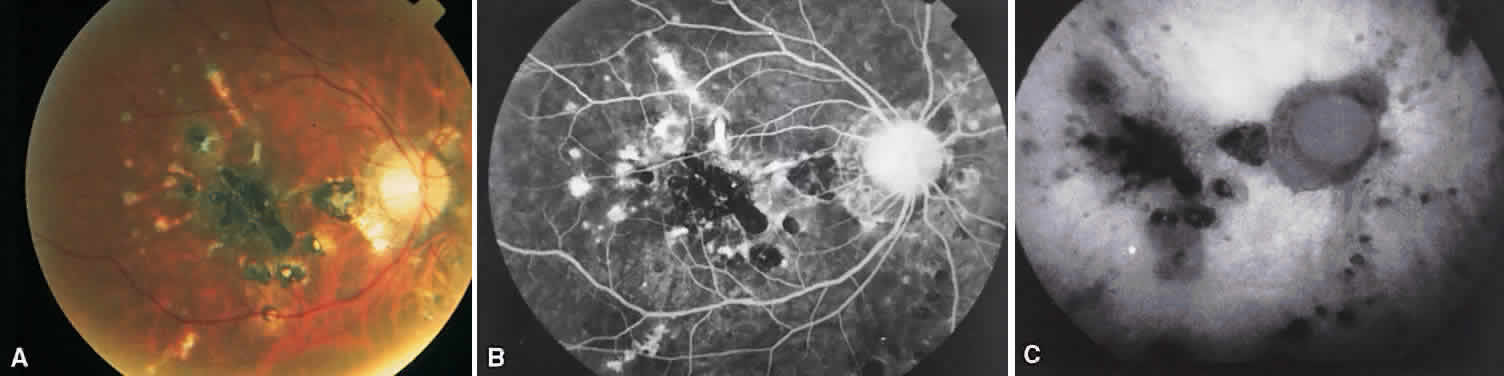

UVEITIS SECONDARY TO PROTOZOA: TOXOPLASMOSIS

Toxoplasmosis is an intracellular parasite with a propensity to infect the inner retinal layers and cause an acute retinochoroiditis. Many cases are the sequelae of an acute intrauterine infection. The acute lesions appear white with prominent vitreous exudate. Often these acute lesions (satellite lesions) are adjacent to old chorioretinal toxoplasmosis scars. Toxoplasmosis also can present as an elevated optic disc swelling, papillitis, and old healed macular lesions (known as macular colobomas), which are sometimes seen with congenital toxoplasmosis (Fig. 27A). Segmental periarteritis, neovascularization of the disc and retina, SRNV, and branch retinal artery occlusion also can be seen (Fig. 28A). A variant form of toxoplasmosis shows multiple gray-white deep retinal or retinal pigment epithelial lesions with minimal overlying vitreous inflammation.

Fig. 27. Congenital toxoplasmosis. A. Recurrent toxoplasmosis retinochoroiditis adjacent to an old scar with surrounding serous retinal detachment. B. Late venous phase angiogram showing discrete pooling of dye in the subretinal space due to an active toxoplasmosis lesion in the superotemporal macula. (Courtesy of Helmut Buettner, MD.)

Fig. 28. Branch retinal arterial occlusion in acute toxoplasmosis. A. Red-free photograph of a superior temporal branch retinal arteriolar occlusion caused by acute Toxoplasma retinitis. B. Angiography shows evidence of a branch arteriolar obstruction with late staining surrounding the area of retinitis (arrow).

On fluorescein angiography in congenital toxoplasmosis, the acute macular lesions hypofluoresce early and hyperfluoresce late. Often there is extensive, complete loss of the retinal pigment epithelium and choriocapillaris, resulting in a hypofluorescent region with possible hyperfluorescence of scar tissue.

On fluorescein angiography, the acute lesions hypofluoresce in the early phase and hyperfluoresce in the late phase (see Fig. 27B).86,87 Old toxoplasmosis scars show hypofluorescence due to loss of the choriocapillaris.88 Various entities can be seen on fluorescein angiography, including branch retinal arteriole occlusion (see Fig. 28B),87,89,90 retinochoroidal anastomosis,91–93 retinal neovascularization,94 and SRNV.95 If papillitis occurs, there are dilated disc capillaries and late disc leakage.96 Segmental periarteritis seen clinically does not usually produce intravascular leakage, vessel staining, or alteration in flow.96 Cystoid macular edema is a rare finding.97 In the atypical deep retinal presentation of toxoplasmosis, there are minimal areas of hyperfluorescence that do not correspond to the clinical, deep retinal lesions.98

On ICG angiography, the main focus of retinochoroiditis is hypofluorescent in all phases of the angiogram, but late-phase (35- to 45-minute) hyperfluorescence also has been observed. The most striking feature, however, is multiple hypofluorescent satellite dark dots. In many cases, the hypofluorescent areas are not seen on FA and clinical examination, suggesting that toxoplasmic retinochoroiditis is a more widespread process than is clinically suspected because it extends beyond the visible lesions. After antitoxoplasma therapy, satellite dark dots disappeared from most of the cases reported. Further, the hypofluorescence under the main lesion was markedly reduced or disappeared in some cases.99–101 A case of toxoplasmic frosted branch angiitis was reported in both eyes of a 10-year-old boy. ICG angiography showed late-phase hyperfluorescence along the frosted vessels and in the disc. Delayed filling in the choriocapillaris also was identified in this child.102